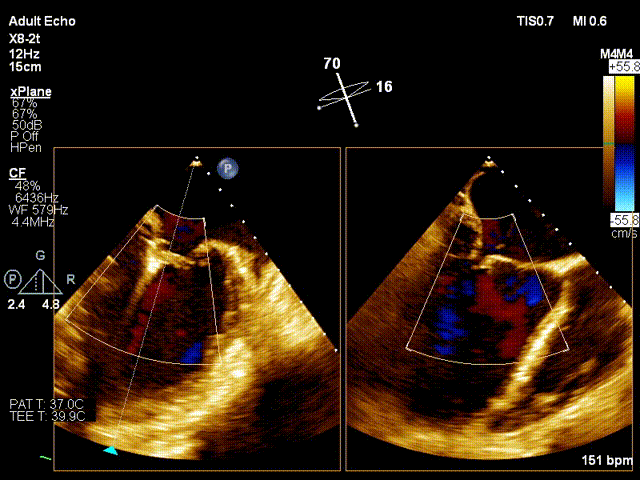

之后迅速调整夹子位置,准确的捕获二尖瓣叶,完成了夹合。术后即刻(植入第一个夹子)TEE示:二尖瓣反流降低至中度,二尖瓣压差6mmHg;测定左房压力:23/20/17mmHg。

第一个架子后